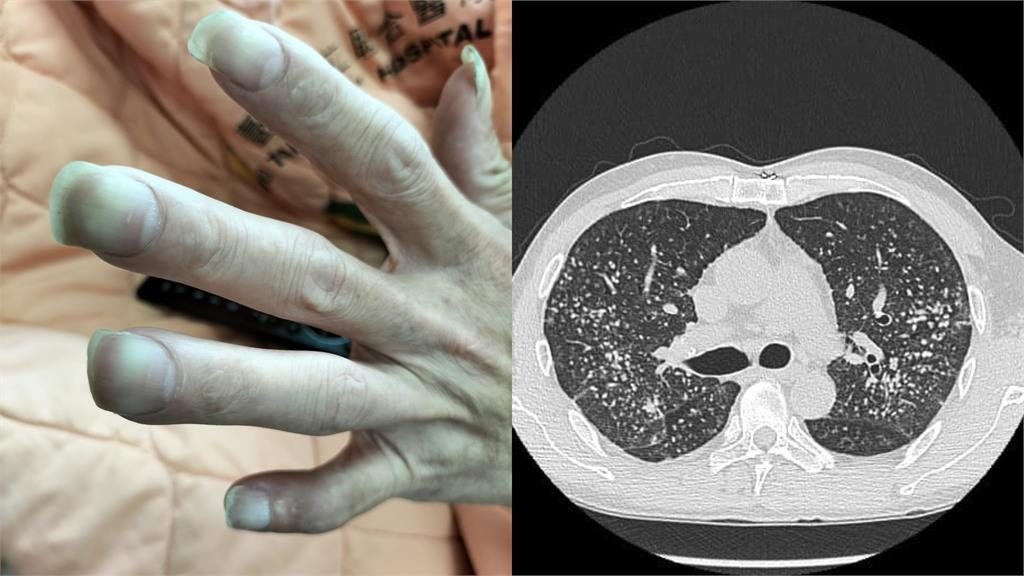

胸腔內科醫師蘇一峰在昨(24)日臉書表示,1名40歲不吸菸的男患者連續喘了好幾個月,因此到胸腔科就醫檢查,結果一看到這名患者十隻手指頭呈現鼓棒,末端近指甲地方則有變大的「杵狀指」,嚇得趕快安排他照X光。透過X光片看到了「滿天星的肺結節」,成千上萬顆肺結節,讓密集恐懼症的人頭皮發麻。

蘇一峰最後也提醒,「看到手指變成杵狀指,記得找醫師檢查一下」。對此,網友見狀也好奇留言詢問「這是什麼病」?而根據衛福部健康署的資料,其實杵狀指並非疾病,而是一種「肢端末梢肥大」的症狀,常造成指甲床跟指節的角度變形。若將雙手十指第一節靠在一起,2個指節的指甲間密合無縫隙的,就可能是所謂的「杵狀指」。